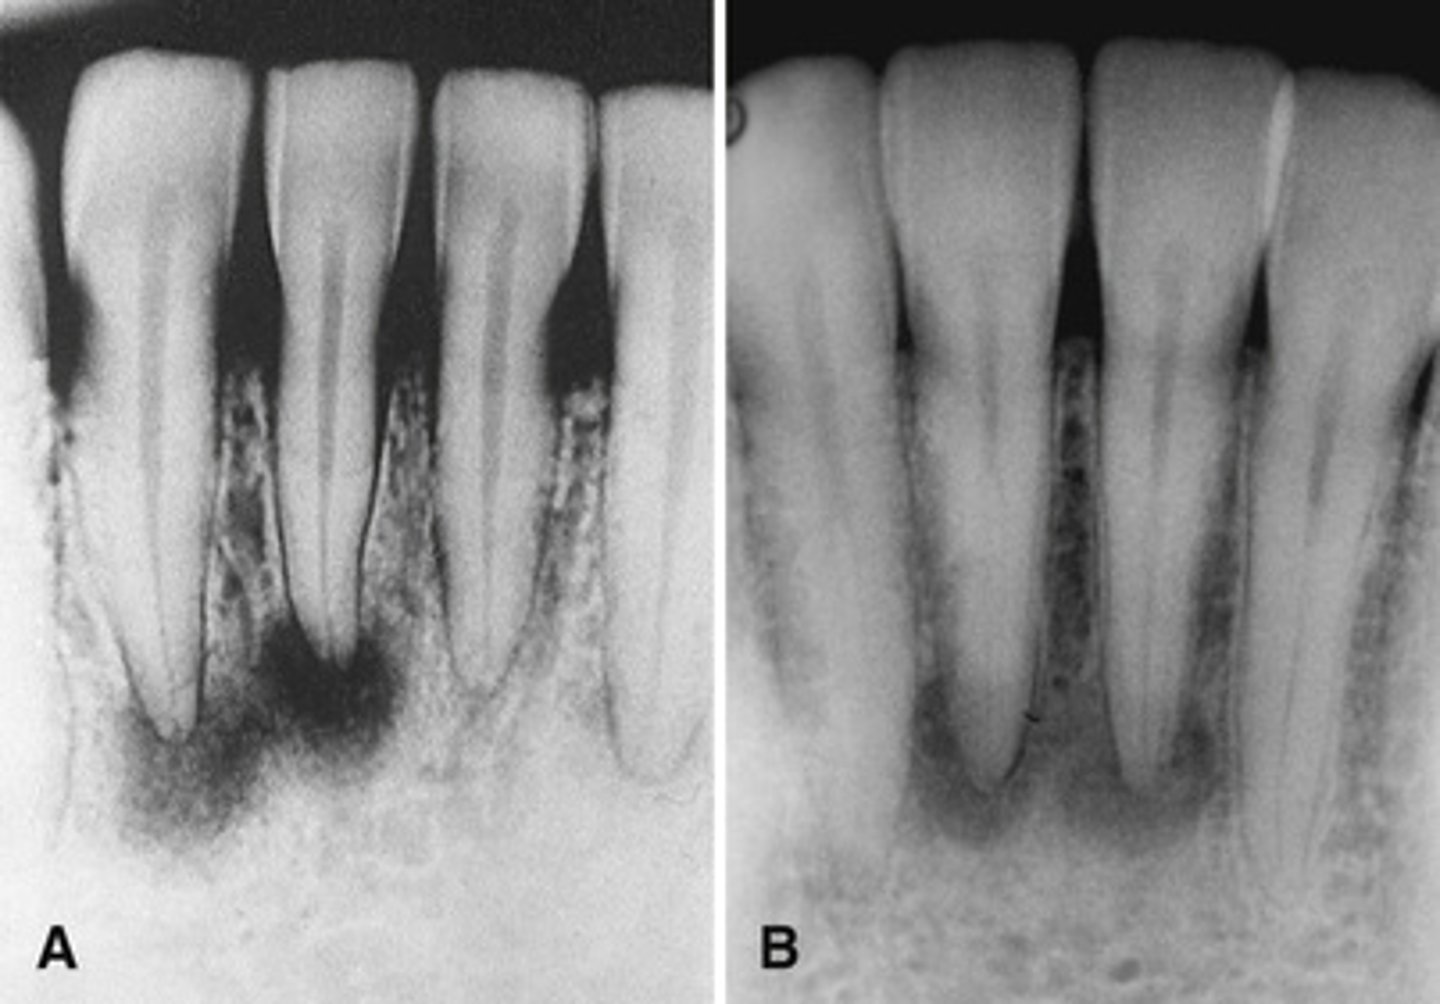

hyperparathyroidism; Brown tumor (aka central giant cell granuloma)

The top images show show loss of lamina dura around the teeth in a patient with _____________. The bottom image shows ________ developing under the molar?

Brown tumor in a patient with hyperparathyroidism

What is the pathology in the radiographs?